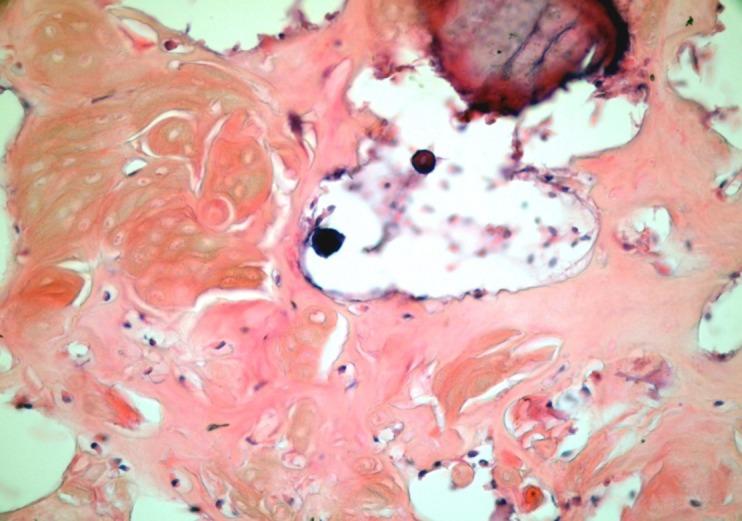

This paper aims to present both intraosseous and extraosseous variant of dentinogenic ghost cell tumor as well as a review of the literature. An 11-year old female patient presented a swelling and pain in the molar area of the mandible and a 15-year-old female patient reported a complaint of swelling in the right vestibular region of teeth 12 and 13(FDI 2-digit classification system). Microscopic examinations showed similar features which characterized by ameloblastoma-like islands of epithelial cells, containing numerous ghost cells. The patients have been disease-free for one year. This paper aims to describe this rare tumor and to increase the number of cases in the literature to better understand its biologic behavior and treatment options.